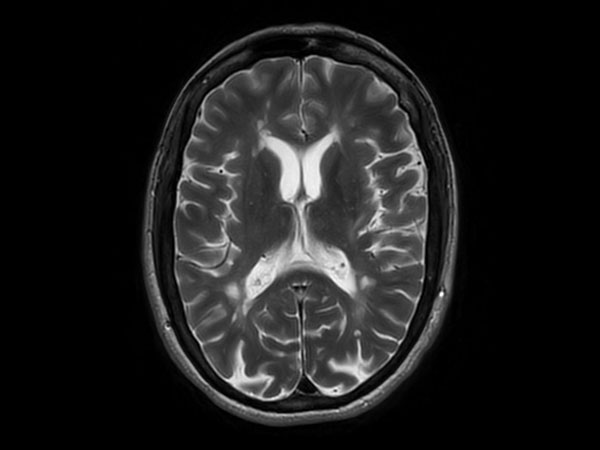

T2w TSE MultiVane XD